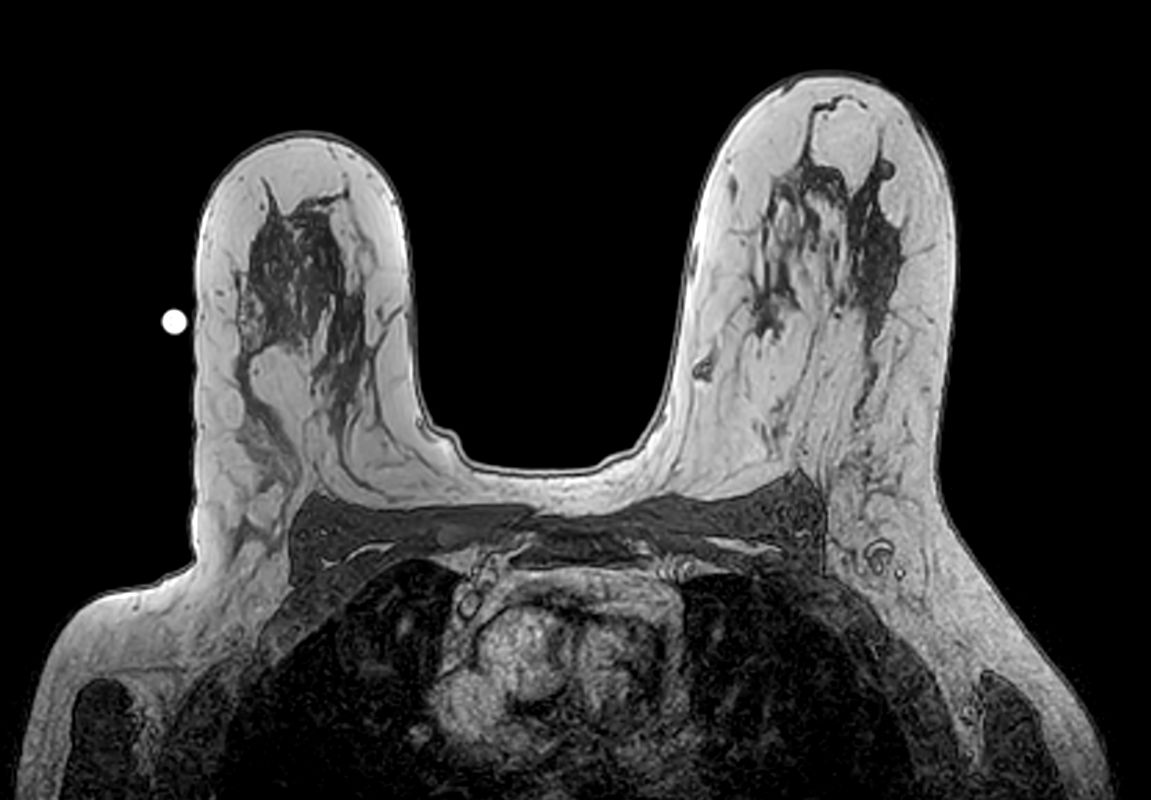

Axial 3D T2w BreastVIEW